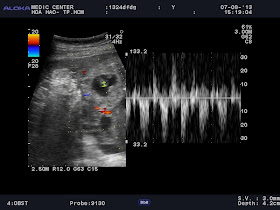

Ultrasound detected an 27x17mm intragastric cyst which adhered the greater curvature. The cyst wall had 2 layers: echogenic inner mucosal lining and hypoechoic outer rim which was contiguous with the muscular layer of the stomach. So we met a muscular rim sign of a  non-communicating GDC (gastric duplication cyst) in adult.